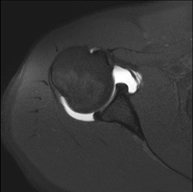

- Shoulder MRI

Examination to study injuries to tendons, muscles and joints. Its main use is to diagnose injuries to the rotator cuff tendons. It lasts approximately 20 minutes. It is a radiation-free procedure.

- Shoulder MRI arthrography

Examination to study injuries to small anatomical structures of the joint that are commonly injured in patients suffering from dislocation or chronic instability. Prior to the examination, a contrast fluid is injected into the joint, guided by X-ray imaging. The total duration of the two procedures is 50 minutes.